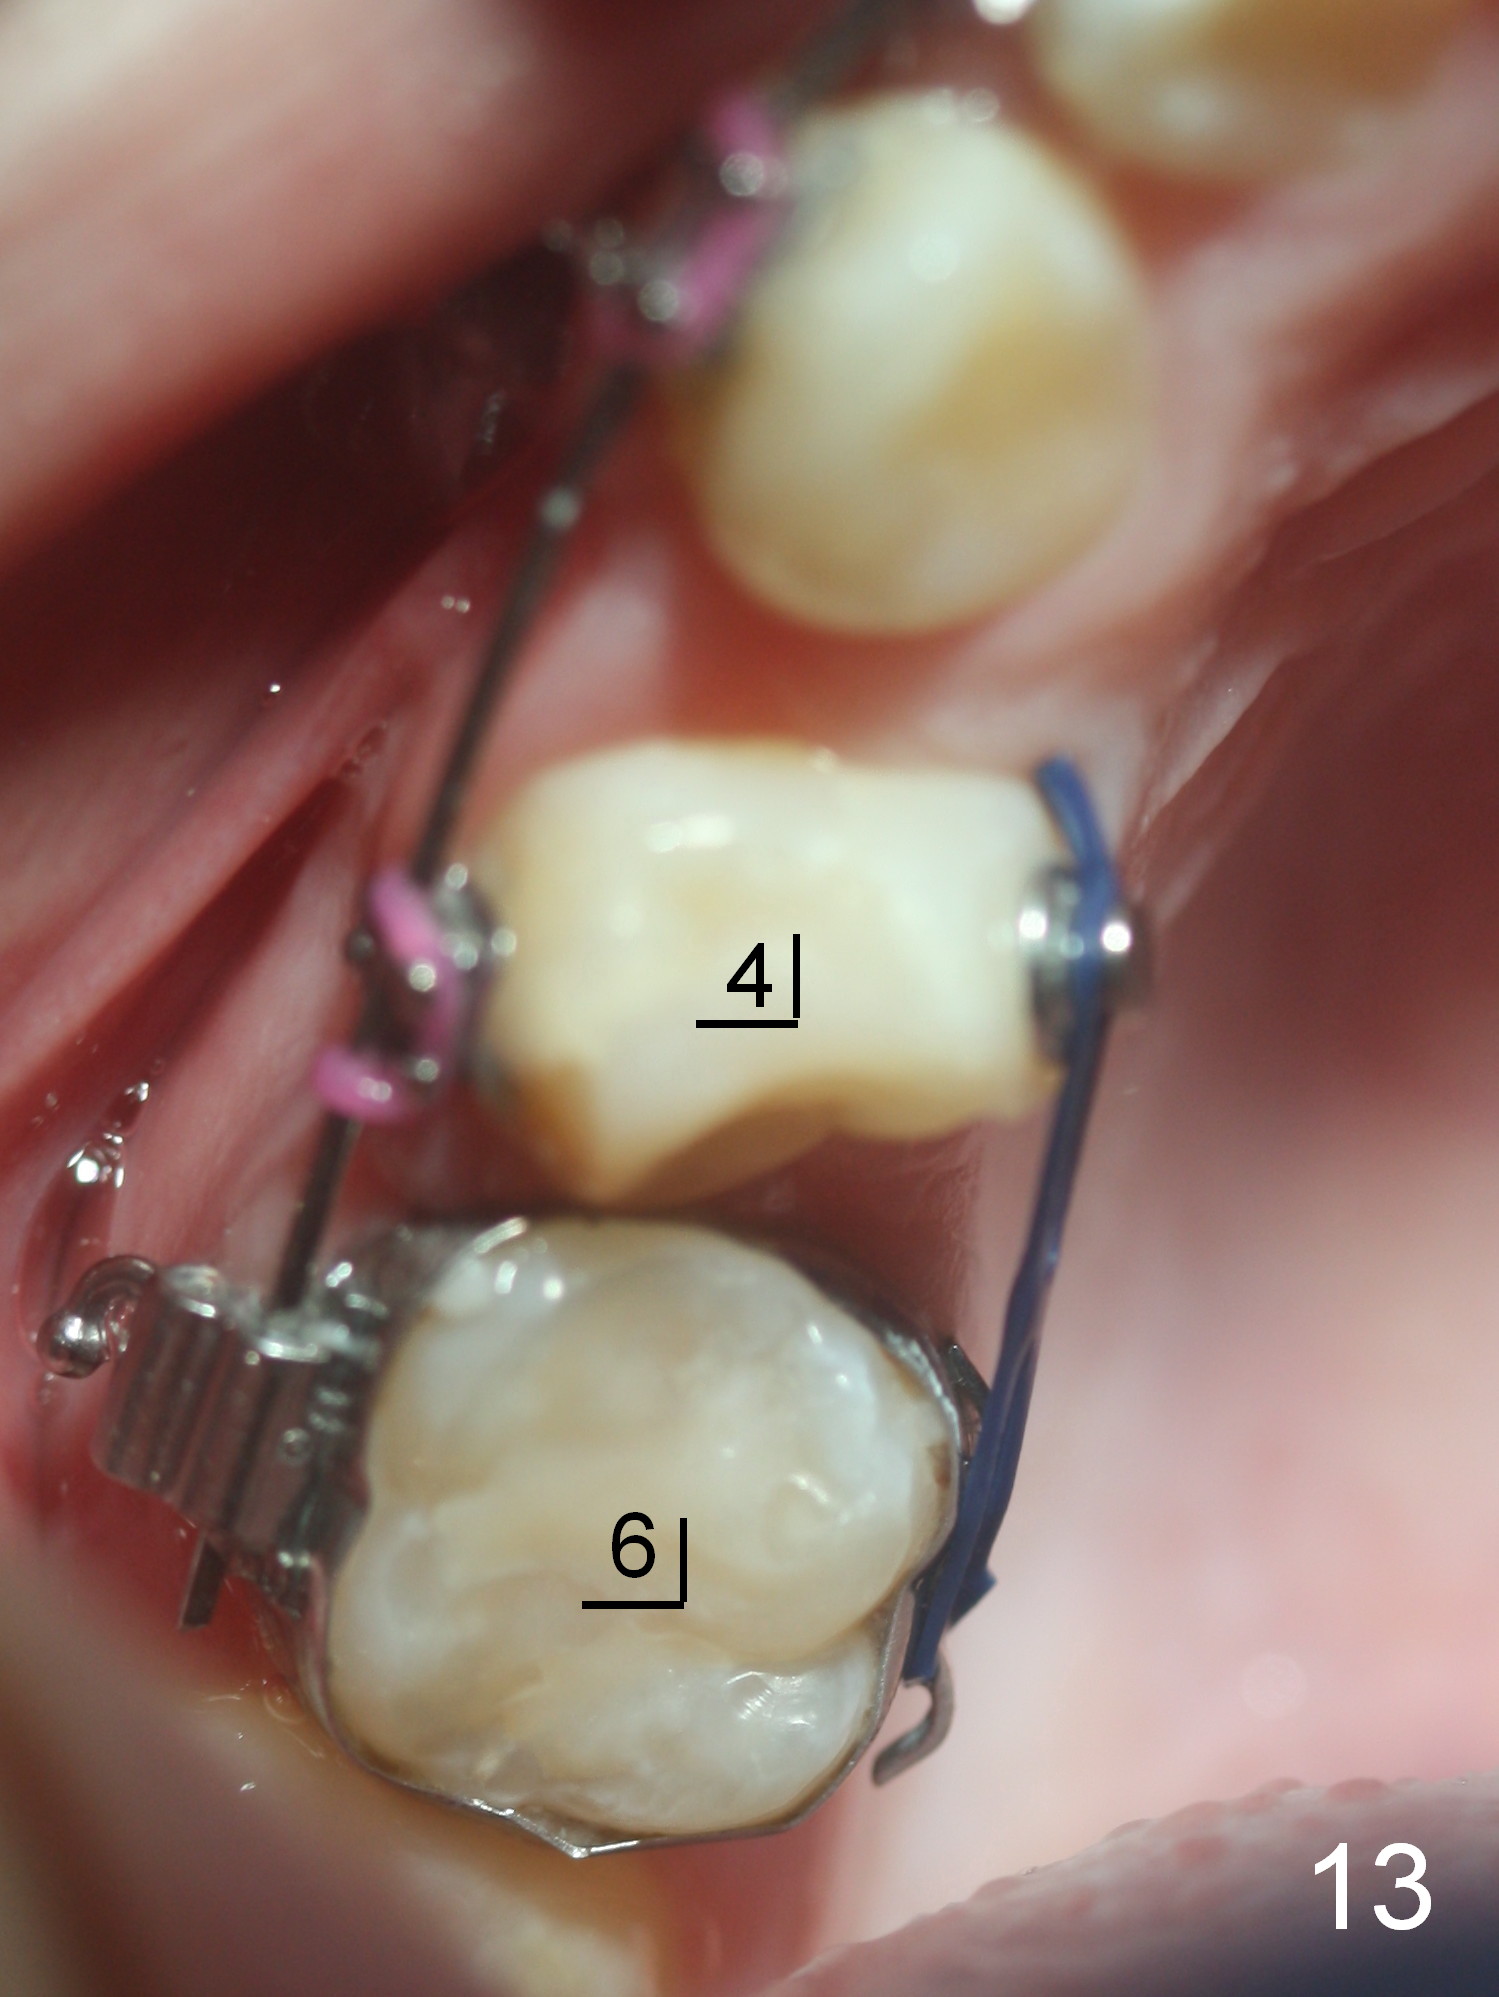

Approximately 4.5 months of power chains between 4s and 6s buccally, U4s contact U6s with rotation (Fig.13,14), while L4s have 1-2 mm to be distalized (Fig.15,16). With placement of lingual buttons on U4s and power chains lingually, the rotation should be corrected. The rotation wedges were placed with ligature wire on the left in the last visit. The patient returns 3 weeks later.